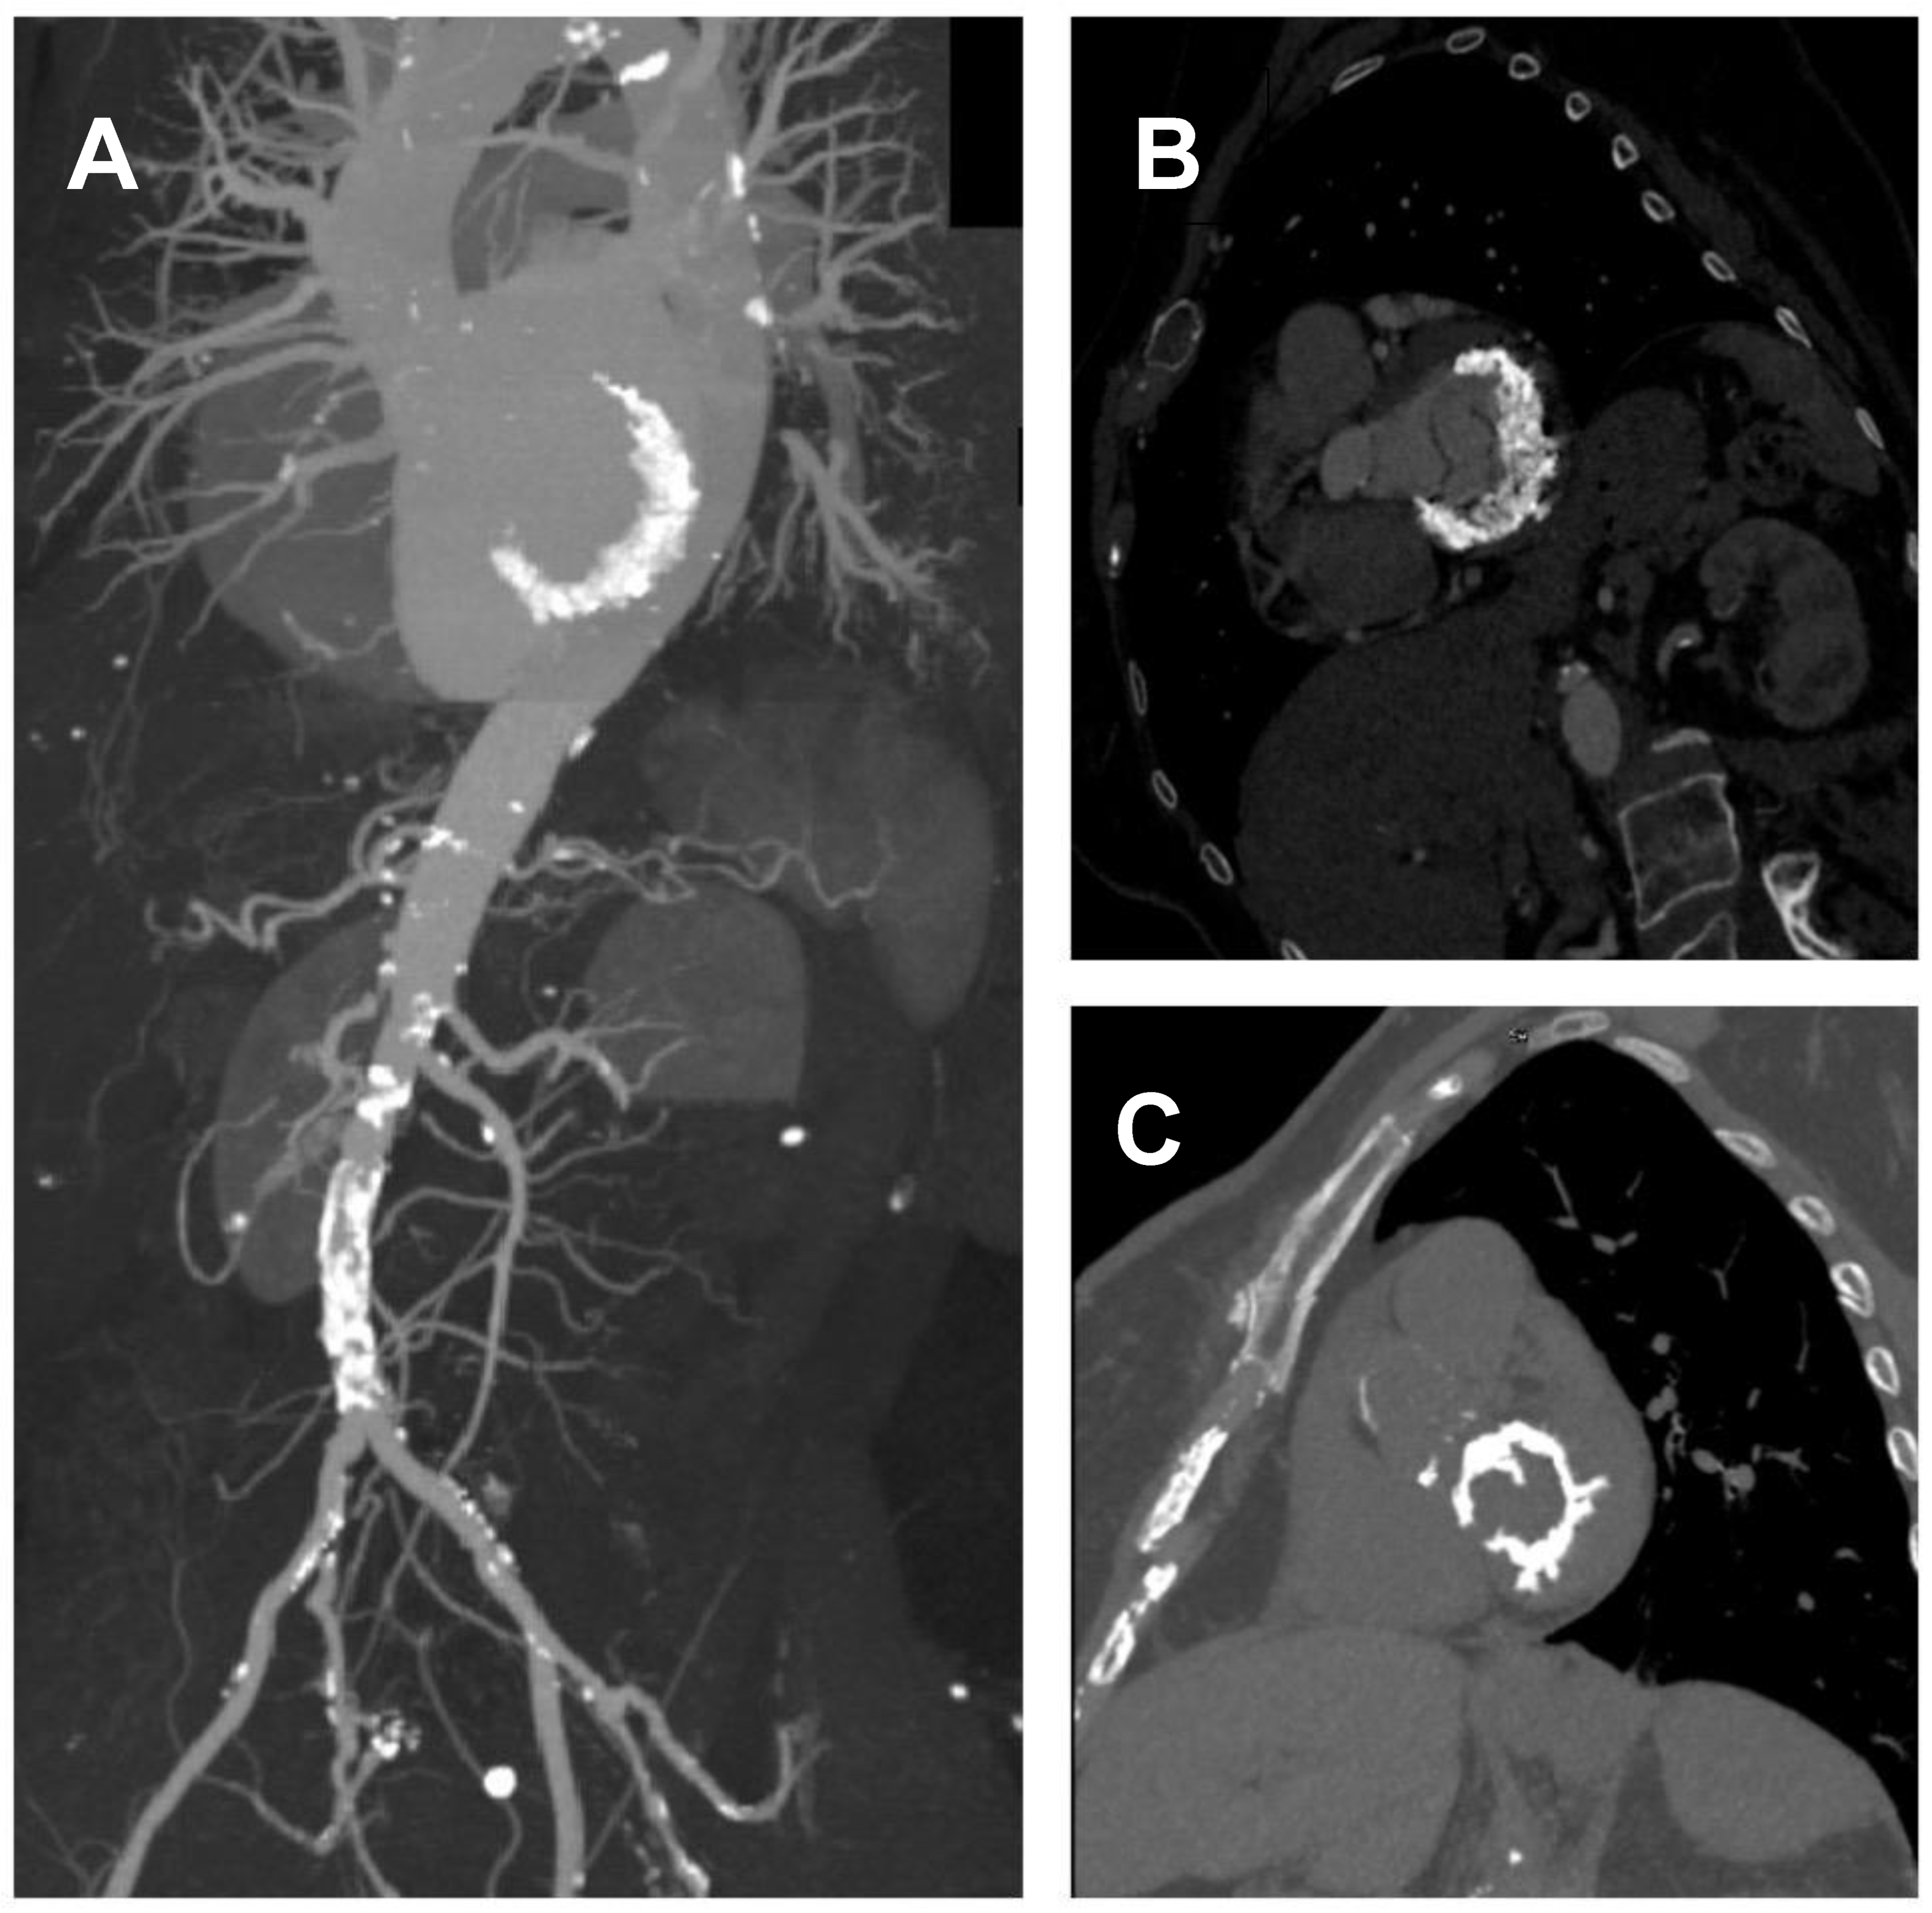

2.3. Computed Tomography Imaging